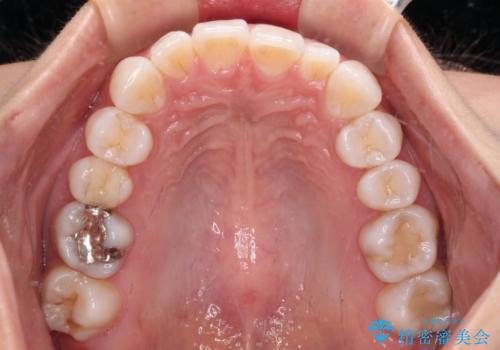

【モニター】前歯のデコボコと小さい前歯 インビザライン矯正とオールセラミッククラウン補綴治療

- 前歯の歯並びと生えてきたときから小さい前歯を気にして来院された患者様です。

上下前歯の歯列不正はインビザラインにより整え、その後に、矮小歯の前歯をオーダーメイドタイプのオールセラミッククラウンにて補綴治療することとしました。

インビザライン矯正の場合、矮小歯を矯正治療後にセラミックとするかどうかを矯正治療開始前に決める必要があるため、悩んでしまう方が多いです。

セラミッククラウンにて大きさを変更することを前提に矯正治療を開始したため、大変満足のいく仕上がりとなりました。